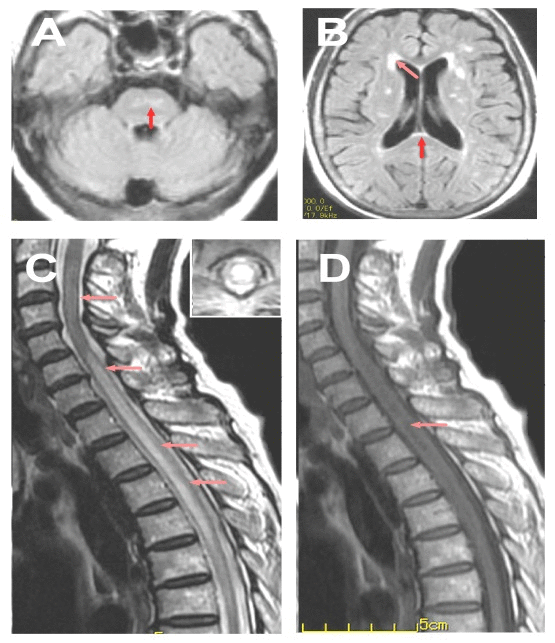

| Figure 1: MRI features of the case. A: Lesion in Pons (arrow); B: Brain lesions around the bilateral ventricle (arrow) and in corpus callosum (arrow); C: T2-weighed spinal MRI showed extensive lesion in the cervical and thoracic cord (C3-T5); D: T1-weighed spinal MRI showed hypointensity mainly around the central canal (arrow). |